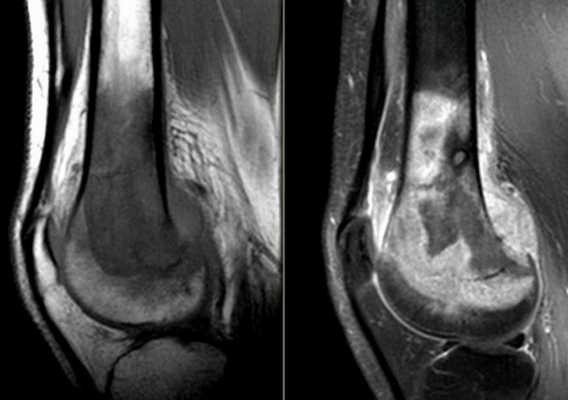

![Остеосаркома бедренной кости на снимке коленного сустава]()

Остеосаркома бедренной кости на снимке коленного сустава

Для уточнения локализации и размеров патологического очага врач может использовать пространственное изображение области интереса . На основании фотографий, полученных в результате сканирования, реконструируют 3D-модель рассматриваемой зоны. Трехмерная визуализация позволяет оценить характер взаимодействия здоровых и пораженных тканей.